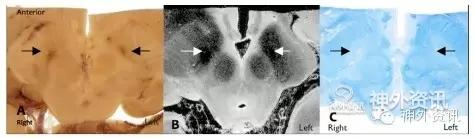

在9.4T MRI上,电极轨道清晰可见,两侧的电极轨道均经过内囊并终止于STN(图1)。组织病理学检查,低倍镜下可见左侧电极位于STN内侧,临近未定带;右侧电极经过STN中央。高倍镜镜检可见电极周围组织内包含有淋巴细胞、胶质细胞、小胶质细胞、巨噬细胞和少量多核巨细胞。

图1. 通过STN平面的组织病理学切片(A)、9.4-T T2轴位MRI图像(B)和坚牢蓝-甲酚紫染色切片(C),均可见STN(箭号)。